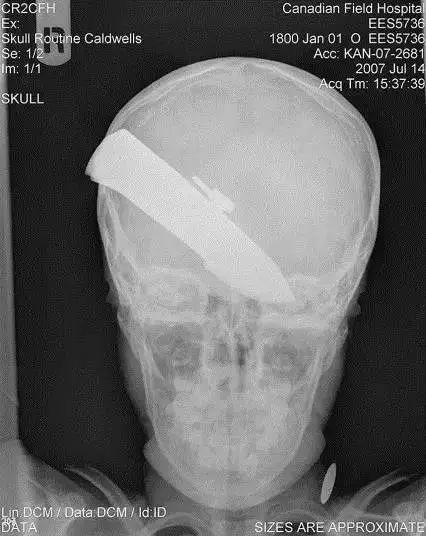

6、这把*首匕**扎入了一名仅有10岁大的阿富汗小男孩的头部,经过手术之后被取出,并在医院接受后续治疗。